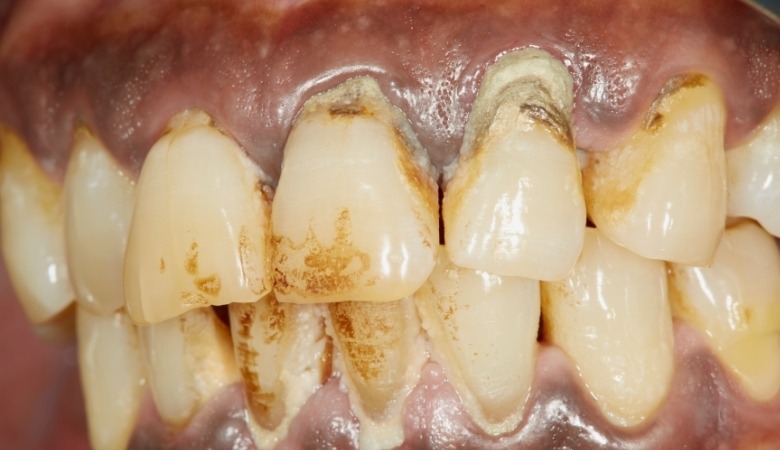

Cao răng (vôi răng) ban đầu chỉ là những mảng bám mềm mại (do vụn thức ăn để lại), nhưng theo thời gian chúng sẽ cứng lại do quá trình vôi hóa, tạo thành một lớp cặn cứng bám chặt trên bề mặt răng và dọc theo đường viền nướu. Cao răng có thể không màu hoặc hơi ngà, thậm chí sẫm màu hơn như nâu hoặc đen nếu tích tụ lâu ngày.

Cao răng có thể hình thành ở bất kỳ vị trí nào trên răng, nhưng phổ biến nhất là ở những khu vực khó vệ sinh như kẽ răng, mặt trong của răng hàm dưới và dọc theo đường viền nướu. Khi cao răng đã hình thành, chúng không thể được loại bỏ bằng việc đánh răng thông thường mà cần đến sự can thiệp của các biện pháp chuyên nghiệp tại nha khoa.

Cao răng là lớp cặn cứng bám chặt trên bề mặt răng có chứa nhiều vi khuẩn gây hại (Nguồn: Internet)